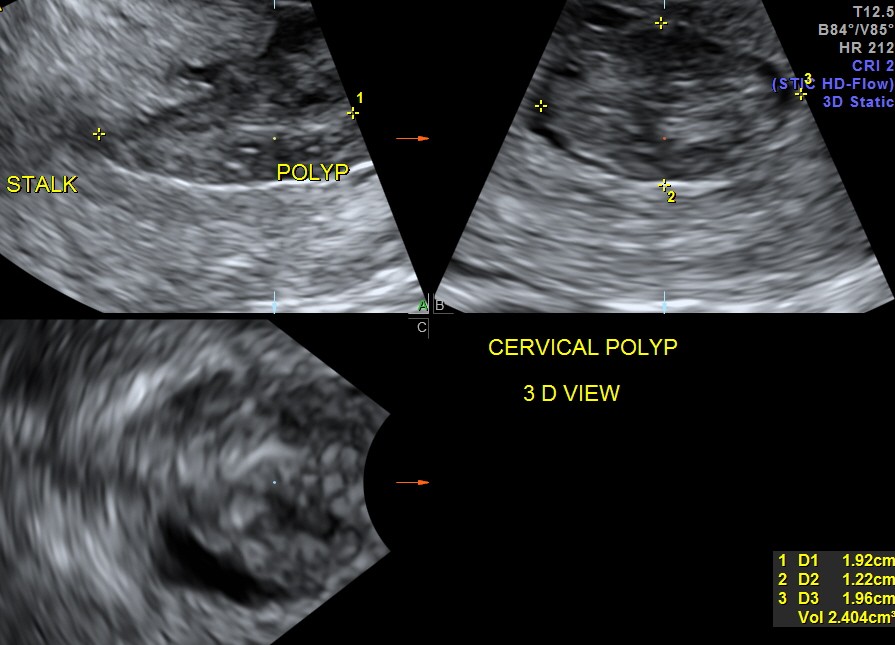

the multi planar 3 d image shows increased flow in the polyp and the stalk arising from the endometrium

The diagnosis offered was an endometrial polyp with a long stalk situated in the cervix.